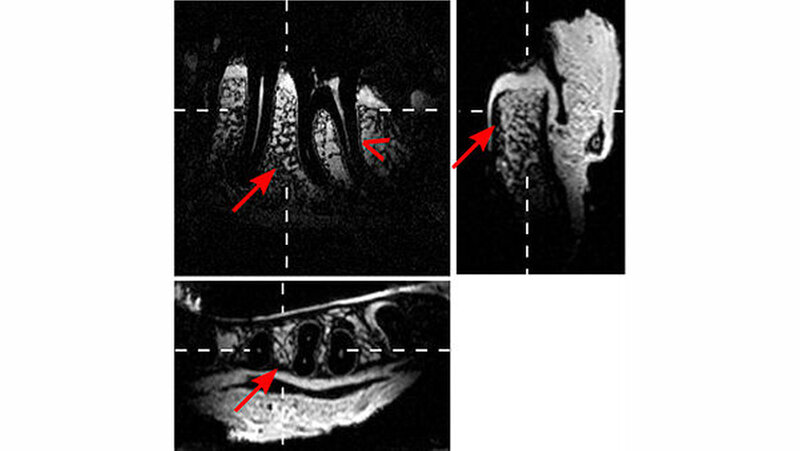

Kieferknochen, Gefäß-Nerven-Stränge und das Weichgewebe werden dargestellt

„Die neue Methode trägt wesentlich dazu bei, dass die Magnetresonanztomografie in Zukunft die konventionelle Röntgendiagnostik in der Zahn-, Mund- und Kieferheilkunde ersetzen wird“, sagt Oberärztin Prof. Katja Nelson. „Vor einer Operation können wir Kieferknochen, Gefäß-Nerven-Stränge und das umgebende Weichgewebe darstellen und so bei der Operation besonders schonend vorgehen, ohne den Nerv zu treffen.“ Da für die Patienten keine Strahlenbelastung besteht, könnten Ärzte die Bildgebung auch erstmals zur regelmäßigen Kontrolle des Heilungsverlaufs einsetzen.

Mithilfe der entwickelten drahtlosen, intraoralen, induktiv-gekoppelten Spulen kann demnach ein MRT in einer ausgewählten Region mit hoher Auflösung in einer klinisch möglichen Zeit von etwa vier Minuten erstellt werden. In der Vergangenheit wurde den Forschern zufolge schon versucht, das MRT-Signal mit Einzelspulen zu verstärken, allerdings ohne durchschlagenden Erfolg. Die jetzt verwendete Doppelspule erlaube nun Bilder von wesentlich höherer Qualität. Dass die Spule kein Kabel benötigt, erleichtere zudem den Einsatz für den Patienten. Die Freiburger Forscher haben die neue Methode bereits patentieren lassen.